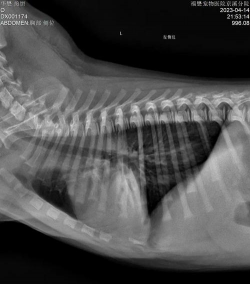

肺线虫感染的诊断基于体征、已知的传播模式和粪便中幼虫的存在。用内窥镜和x射线检查气道可能是有用的工具。兽医诊断肺线虫可能是一个挑战,因为受感染的动物并不总是通过粪便传播幼虫,而且当它们通过粪便传播时,数量可能很少。支气管镜可用于收集气管冲洗液,以检查卵、幼虫和白细胞。